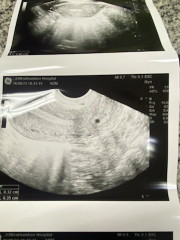

ไปซาวมาผ่านช่องคลอด หมอนับได้ 5w3d จากวัน ปจด มาครังล่าสุด แต่ไม่พบตัวอ่อน เจอแค่ถุงตั้งครรภ์ 0.5 mm อย่ากทราบว่าปกติไหม

ของเราซาวน์ตอน 5w3d เหมือนกันค่ะ หมอเห็นถุงการตั้งครรภ์ไข่แดงน้อง ดูว่าอยู่ในจุดที่ดี ไม่ใช่การท้องนอกมดลูก แต่ยังไม่เป็นตัวค่ะ หมอนัดอีก 2 อาทิตย์ น่าจะเริ่มเห็นตัวน้องน้อยๆ

5wk น่าจะยังไม่เห็นตัวน้องนะคะจะเห็นแค่ถุง น้อง6+wk ขึ้นไปจะเห็นค่ะ เราเคยซาวด์ตอน5wk ไม่เห็นเหมือนกันค่ะ